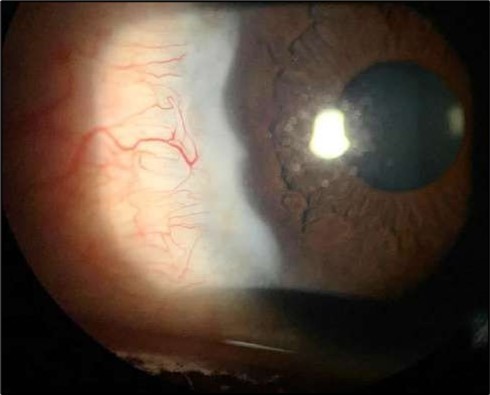

Two weeks post-surgery, the left eye showed significant healing, with a small conjunctival granuloma and vascularization at the ulcer margins. The cornea was clear with a central leading edge nasally, deep and quiet anterior chamber and clear lens. VA 6/6 bilaterally and IOP normal. Histopathology of excised conjunctiva showed non-keratinized squamous epithelium with superficial erosions, stromal elastosis, hemorrhage, and inflammatory infiltration, but no signs of granulomatous disease, malignancy, or viral evidence, findings consistent with idiopathic localized inflammatory process. The patient reported significant relief and satisfaction post-surgery, resuming normal activities. Treatment continued with oral prednisolone 25 milligrams every other day, tobramycin-dexamethasone ointment twice daily, and preservative-free artificial tears four times daily Figure 4, Figure 5a, Figure 5b, Figure 5c, Figure 5d.

Figure 4.OS. Slit-lamp photograph showing a partially quiet ocular surface two weeks following surgical excision of adjacent perilimbal conjunctiva.

At six-months follow-up post-resection, the ulcer showed progressive epithelialization with no recurrence. Oral prednisolone was gradually tapered and stopped. The patient remains under regular ophthalmology follow-up with stable ocular findings Figure 6.

Figure 6.Six-month follow-up image showing a stable ocular surface, and absence of ulcer recurrence. The cornea appears clear centrally, with stromal scarring limited to the periphery.